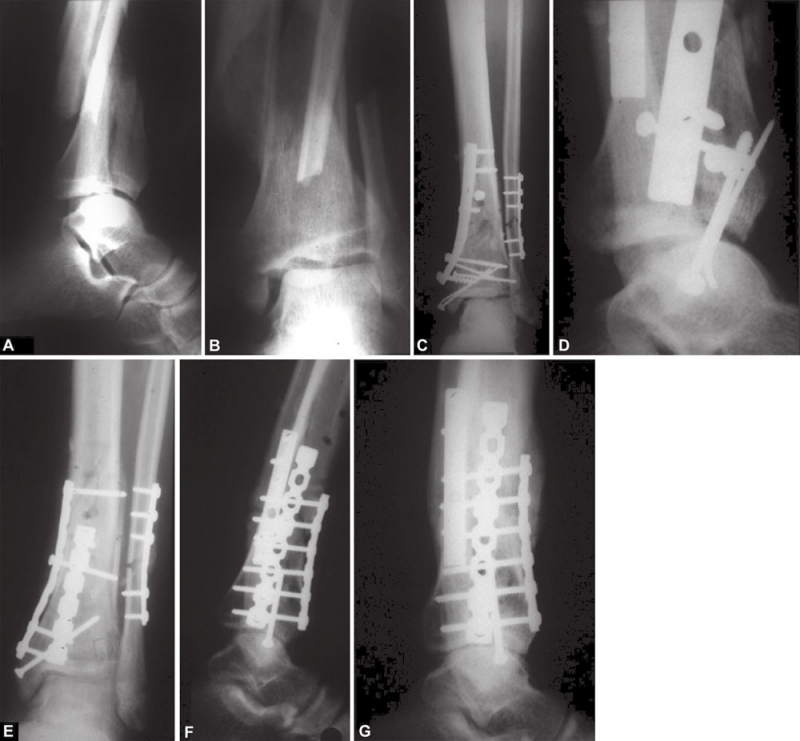

并发症主要有:感染,骨折的缺血性坏死,骨不连或者畸形愈合伴有内翻或外翻,关节的不稳定关节面的不平整,最终的关节炎。只要存在现实改善的机会时,关节的不协调应当尽早进行手术(图20)。

图20 A~G(A~D)固定不充分。Pilon前方部位未复位,没有良好支撑;(E~G)复位后骨折愈合,12个月后显示愈合良好